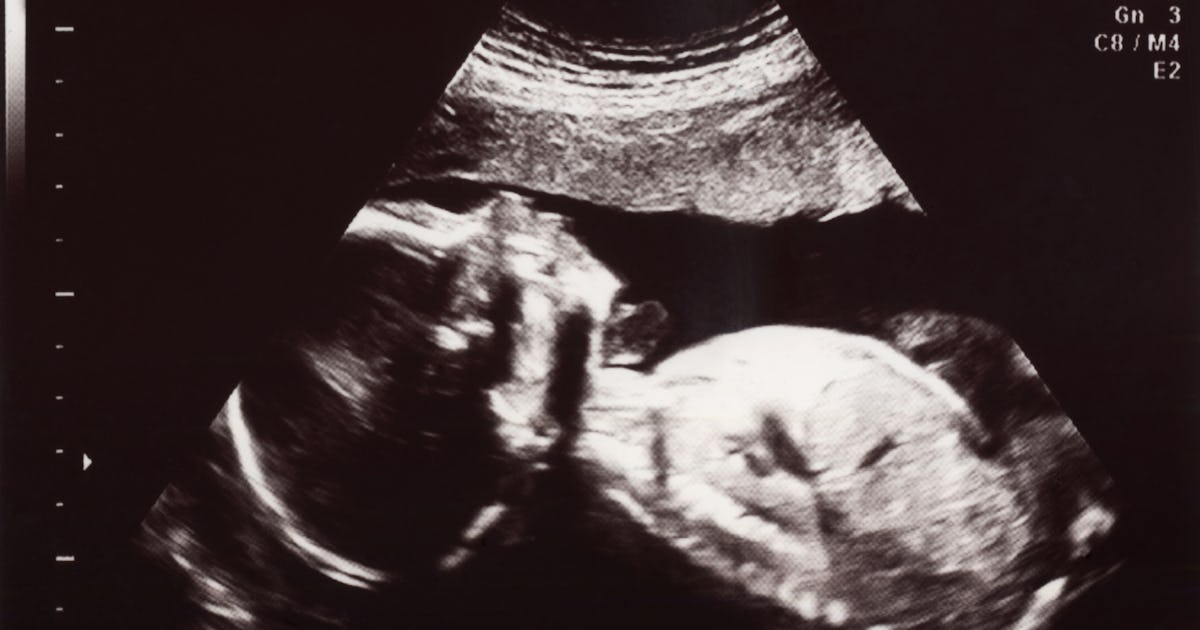

. Babies practice breathing movements with increasing frequency towards the end of pregnancy but usually this is only seen via ultrasound and the mother cant feel OR see. In the third trimester babies do take practice breaths by filling the lungs with even more amniotic fluid but it does not transfer oxygen into the babys body. The baby takes the first breath within about 10 seconds after.

Even after the babys lungs are developed in the womb the baby is surrounded by amniotic fluid and hence even the lungs are filled with amniotic fluid. The contractions squeeze the baby towards the birth canal whilst also simultaneously pushing the amniotic fluid out of the babys lungs in preparation for them to breathe for the first time. Instead oxygen travels through the mothers lungs heart vasculature uterus and placenta finally making its way through the.

Compared with adults babies breathe very fast. During that moment the babys lungs expand with air the flap on the heart shuts to start the circulation from the lungs and the new system of getting oxygen into the blood from the air kicks in. Pin On Nursing At around nine weeks of gestation unborn babies begin to make a breathing movement.